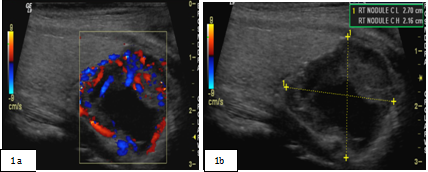

Neck ultrasound (Figure 1A & 1B) revealed a right dominant 2.8cm complex, solid and cystic nodule with intranodular and peripheral vascularity. She was admitted and was treated with intravenous (IV) normal saline. She received 1 dose of IV pamidronate 60mg. Her calcium level improved to 9.8mg/dl and was subsequently discharged. She underwent biopsy of the right thyroid nodule, which was consistent with parathyroid neoplasm possibly adenoma with immunohistochemistry negative for Thyroglobulin, TTF 1, Calcitonin and S 100. She was subsequently referred to endocrine surgery for evaluation of parathyriodectomy. CT scan of neck with 3D imaging reconstruction2 (Figure 2) study confirmed a large well defined nodule with peripheral enhancement suspicious for large right parathyroid adenoma. She underwent minimally invasive parathyriodectomy with fluid aspiration and intra-operative PTH levels fell from 289 pg/ml to 15.8 pg/ml. Pathology (Figure 3) was supportive of the diagnosis of atypical parathyroid adenoma with fragments of hyper cellular parathyroid neoplasm consisting of neoplastic cells with solid nest and trabecular growth patterns with focal capsular distortion and increased mitotic activity. Immunohistochemistry revealed Ki-67 proliferation index 1-3%, bcl-2 positive, diffuse strong and focal weak positive p 53. Post operatively; she was started on calcium and vitamin D supplementation. She is doing well and remains normocalcemic for 2 years following surgical resection with most recent calcium of 9.3mg/dl.

Figure 2 Localization of parathyroid adenoma on CT of neck with 3 D reconstruction.